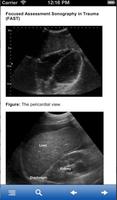

集中的な評価超音波外傷